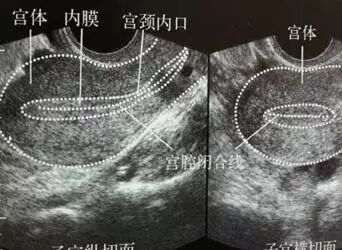

(图:B超下示子宫内膜)